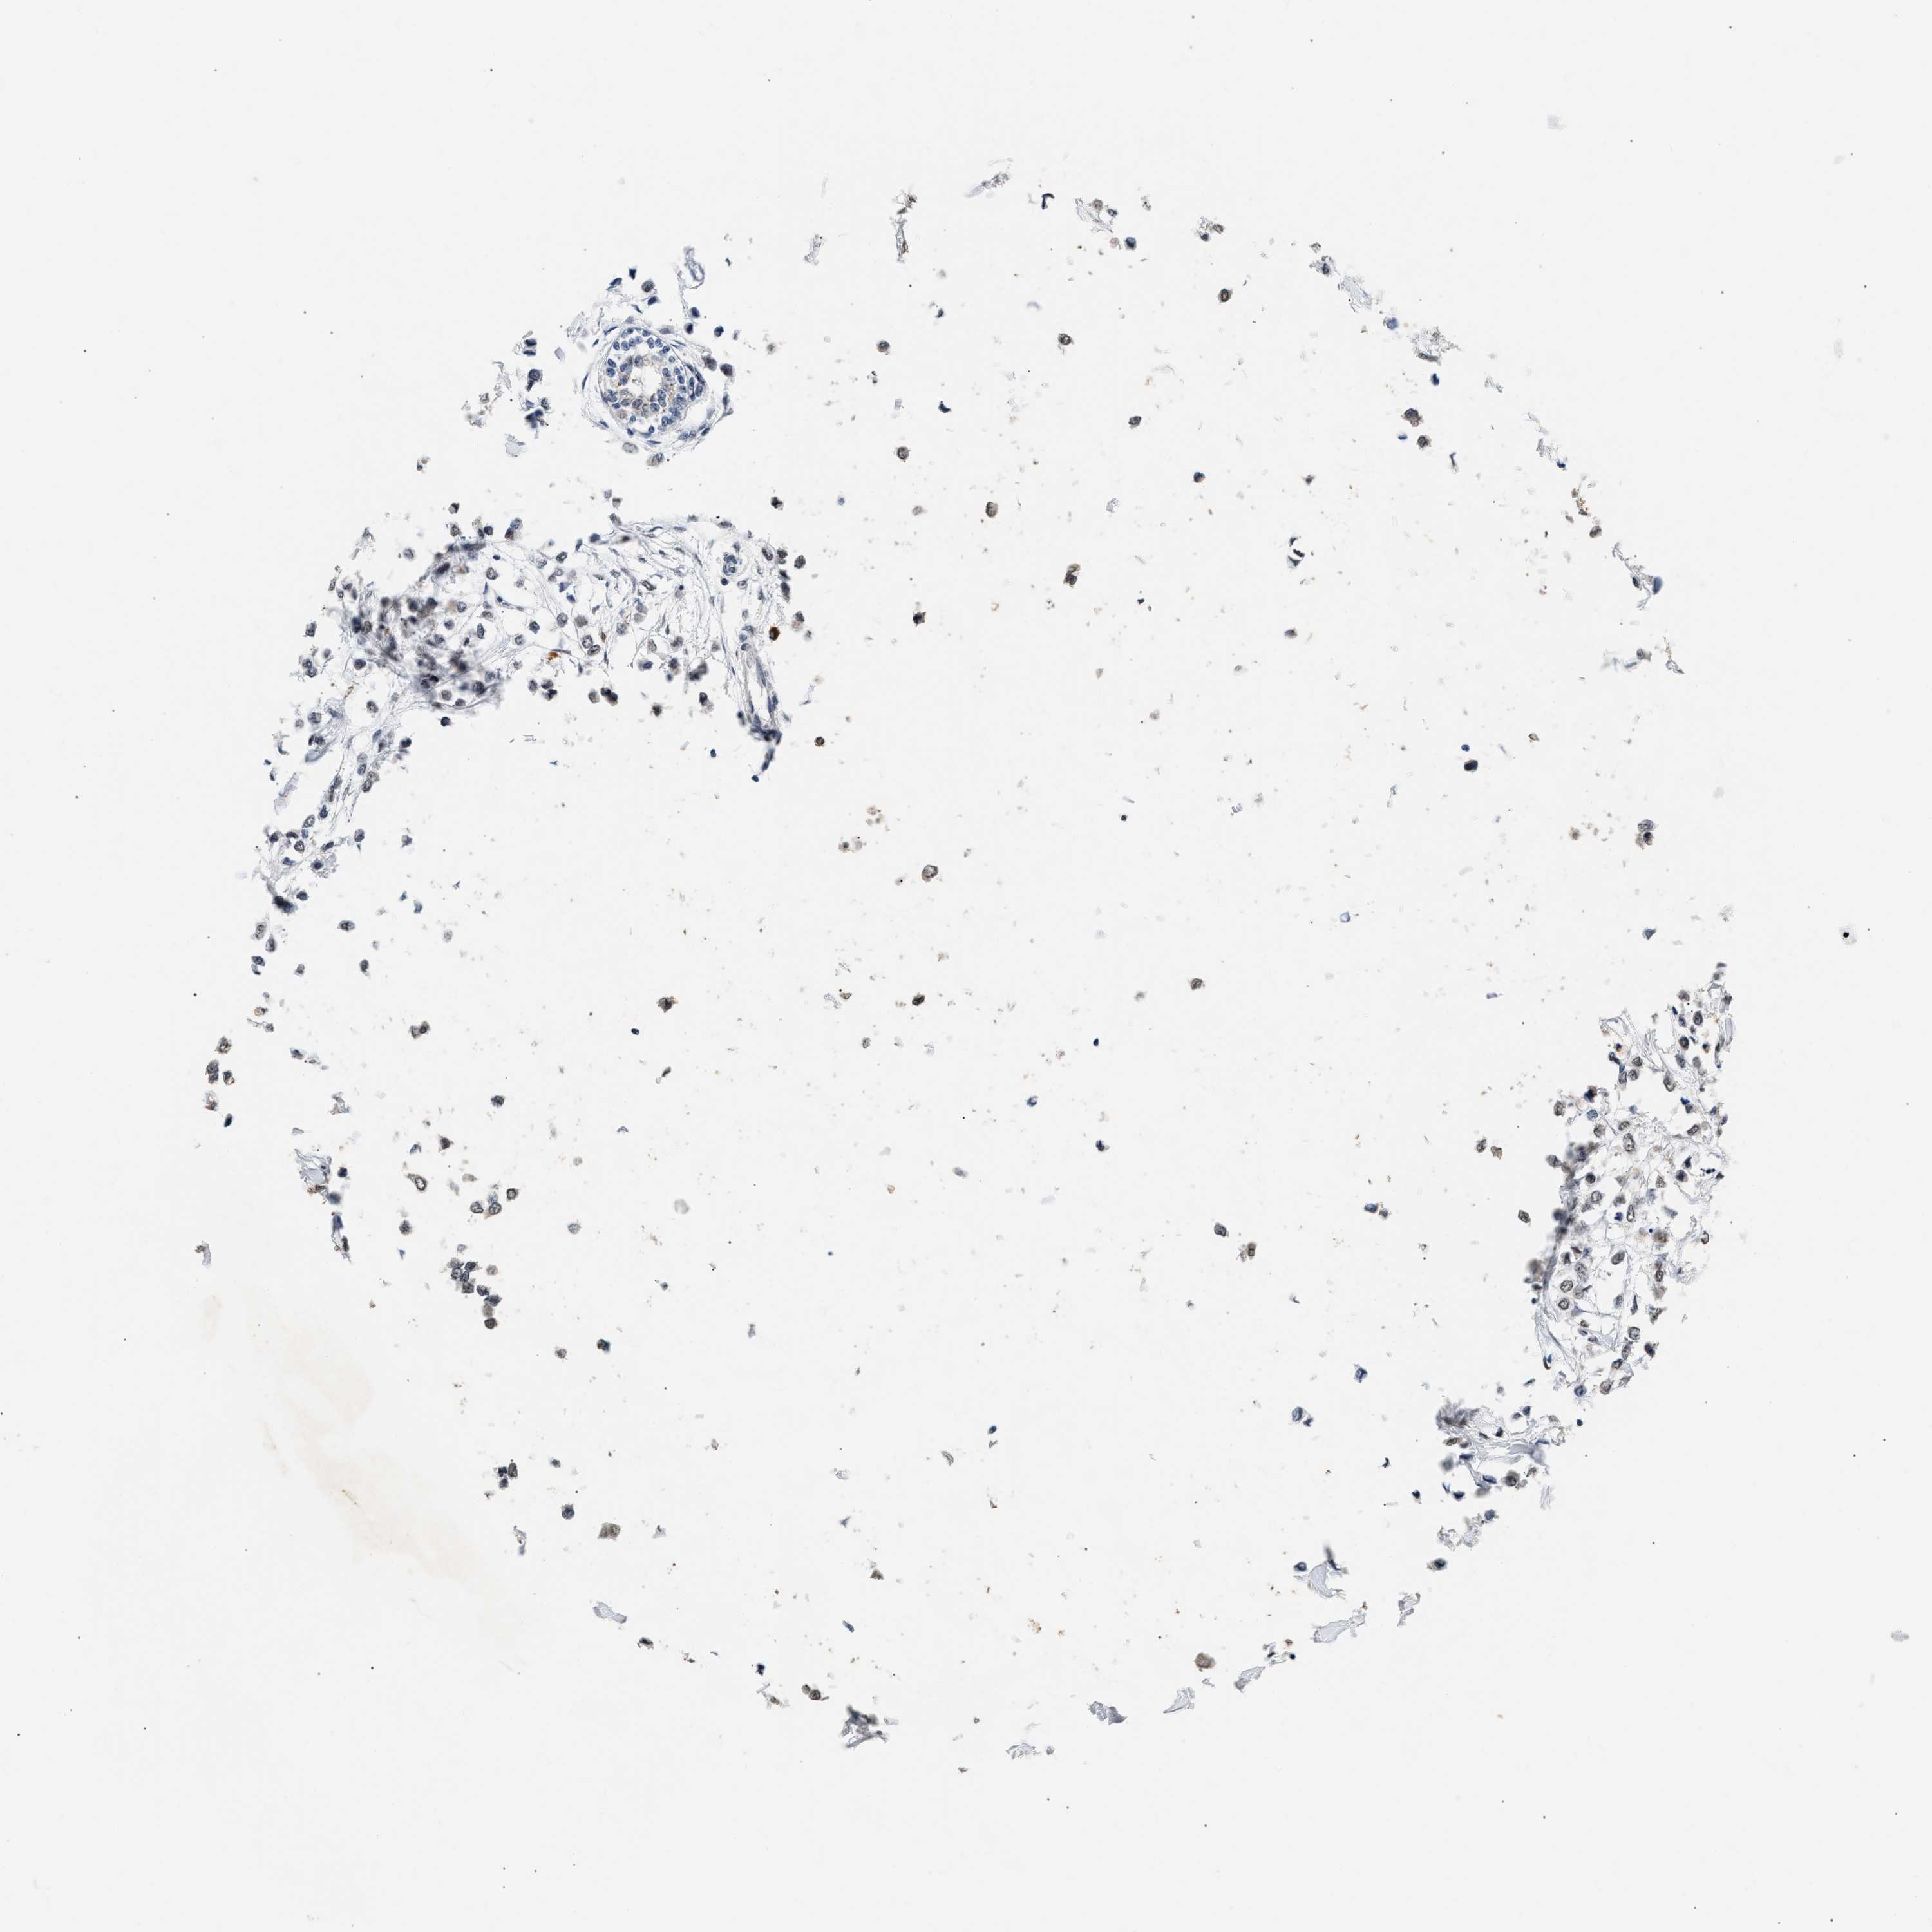

CANCER BREAST CANCER Show tissue menu

BRCA TCGA BRCA VALIDATION PROTEIN EXPRESSION